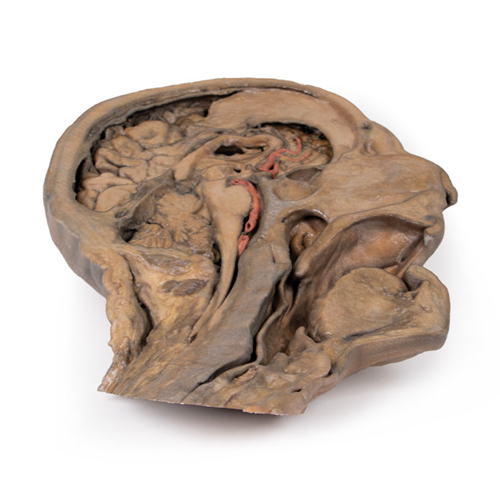

- 解剖模型

- 顔

- 頭部

- 3Dプリント

| 特長 | 本製品の説明は英語のみです。 Product information "Parasagittal Section of the head and neck" This 3D model of the head and neck represents a specimen sectioned just off the midsagittal plane to retain some midline anatomical structures (e.g., the falx cerebri, the septum pellucidum, the nasal septum) that are absent from other specimens in the series. There has also been fixative-induced shrinkage of the neural tissue. This reduction in volume has the benefit of exaggerating the space between the brain and endocranial contours and structures which are normally in closer approximation. The undissected side of the specimen has been digitally removed. The anterior part of the falx cerebri has been retained from its anterior attachment at the crista galli to roughly the midpoint of its extent towards the tentorium cerebelli. At the attachment of the falx part of the dura has been removed to demonstrate the extent of the superior sagittal sinus within the retained portion of the dural infold. The brain itself has been sectioned with preservation of the septum pellucidum and the interventricular foramen (of Monro) defining the passageway between the deep lateral ventricle and sectioned third ventricle. This section plane also captures the infundibulum extending from the hypothalamus to the pituitary gland, which is seated adjacent to a well-developed sphenoid sinus. Both the cerebral aqueduct and fourth ventricle are preserved, as are parts of the left vertebral artery, left posterior cerebral (in cross-section) and the branches of the anterior cerebral artery passing around the corpus callosum. The retention of the nasal septum in this specimen (and in contrast to other 3D models of the head and neck in the series) allows for an appreciation of the relationship between the septum and the hard and soft palates, the entrance of the auditory tube, and the overall nasopharynx relative to the nasal cavity and oropharyngeal region inferior to it. The muscular wall of the pharynx has been isolated to demonstrate the position relative to the cervical vertebral column. Inferiorly, the tracheal cartilages including the epiglottis, arytenoid and thyroid have been retained to demonstrate the position of these cartilages relative to the hyoid bone, as well as the vestibule, vestibular fold, and vocal fold in cross-section. |